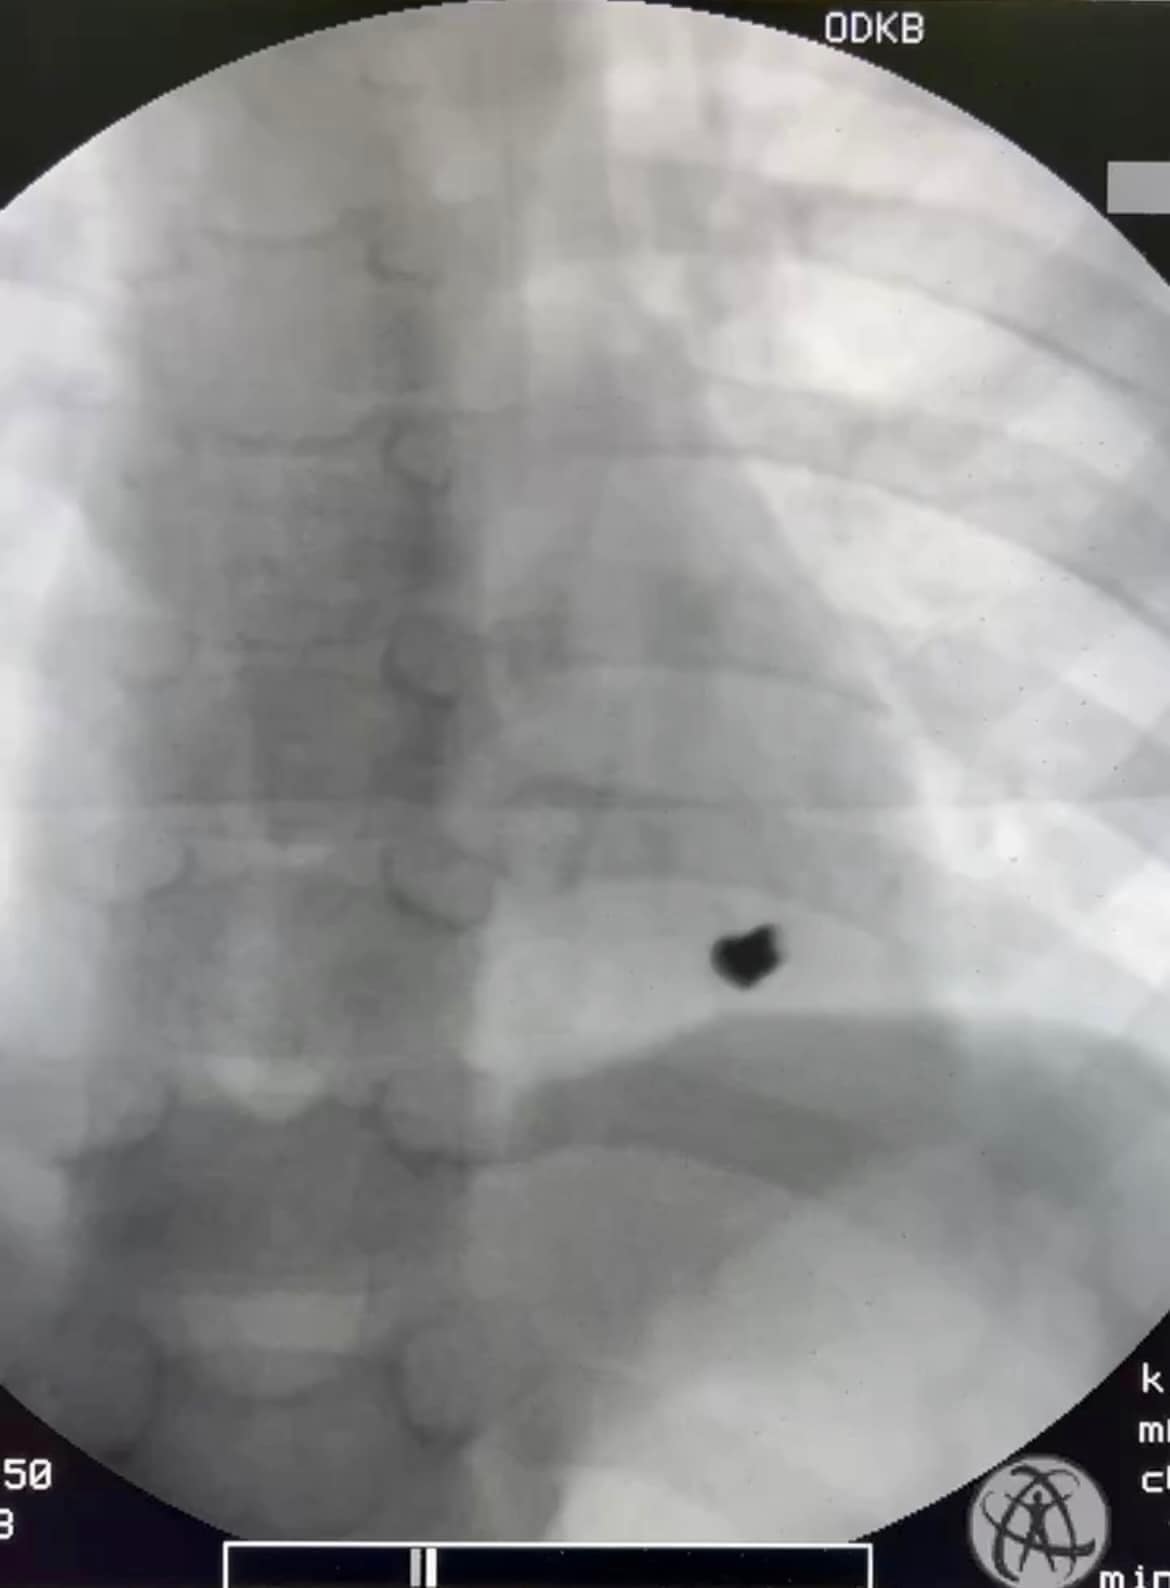

1-го квітня до медичного закладу була госпіталізована 7-річна дитина з травмою серця від кульового поранення. У лікарні зазначили, що гра двох братів 7-ми та 8-ми років гвинтівкою, яка, як потім з’ясувалося, була зарядженою, закінчилася пораненням лівої частини грудної стінки з проникненням кулі в порожнину перикарду (серцевої сумки) та ураженням задньої стінки лівого шлуночку серця.

“Дитина народилася у «сорочці», бо, на щастя, хлопчик був вчасно госпіталізований до Татарбунарської багатопрофільної лікарні та переведений до Одеської дитячої обласної лікарні, де був прооперований в ургентному порядку нашими кардіохірургами – завідувачем відділенням серцево-судинної хірургії Володимиром Бузовським та лікарем серцево-судинним хірургом Олександром Гоцуляком. Вони виконали оперативне втручання на серці та врятували дитину”, – повідомив директор Одеської обласної дитячої клінічної лікарні Павло Георгієв.